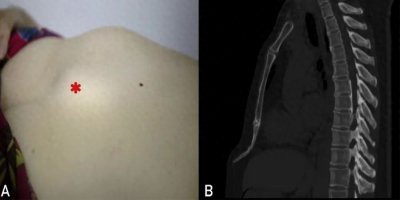

剑突综合征 病例介绍 患者年龄:59岁 患者性别:女 简要病史: 上腹部隆起包块30年就诊。 上腹部中部可见肿块,仰卧位时尤为明显(图 A)。 CT显示一个细长弯曲的剑突(图 B)。 测...